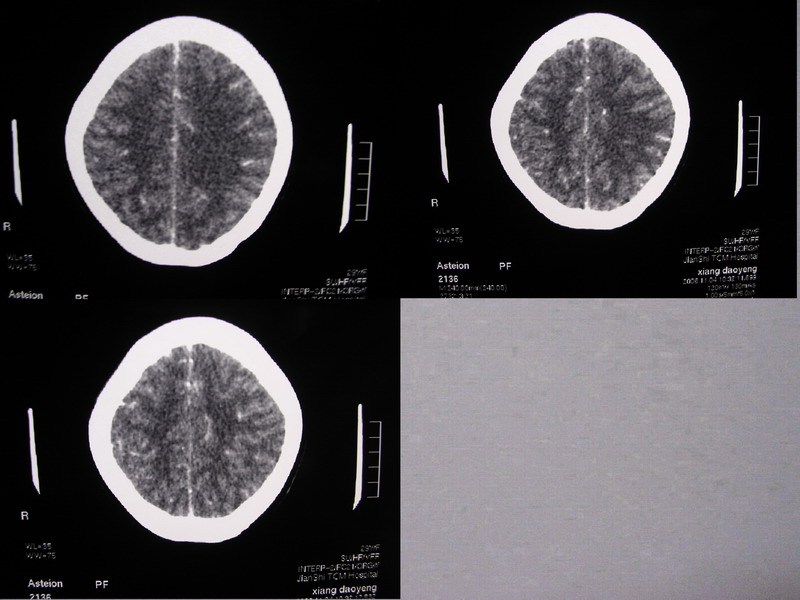

向××,女,29岁,二十天前高热,抗炎治疗后双眼斜视,肌无力,双下肢张力ii级。

除侧脑室额角轻度扩大外,余未见异常。

感觉胼胝体有异常,但看不出异常影像特征,建议行mri进一步确诊.

可能是因为图片太小了,总感觉左侧颞叶和右侧额叶前部看的不是很舒服。

双侧脑室有轻度扩大,增强看脑沟裂显示还是模糊的.时间较长应该考虑脑膜炎.